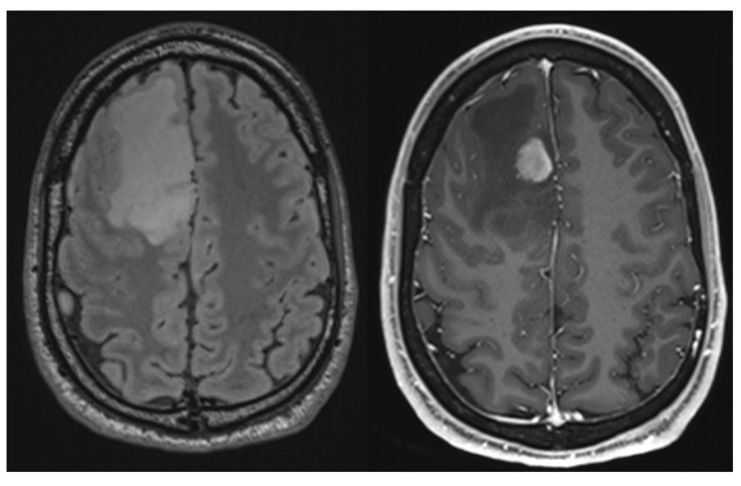

令人惋惜的是,其中 1 例极端病例迅速进展并恶性转化,最终导致患者离世。该患者由外院转诊而来,其前一年的随访资料被原主管医师判断为“未见进展”。待患者 1 年后检查时,MRI 已提示肿瘤发生恶性转化。此时患者出现全面性强直-阵挛发作……

另外一例的进展也很突然:偶然查出时,选择随访,始终未见肿瘤体积增大;然而,第 3 次随访MRI却意外出现局灶性对比增强,遂决定立即手术。